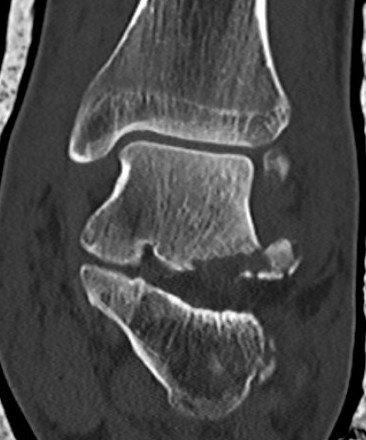

Fracture lateral process of talus